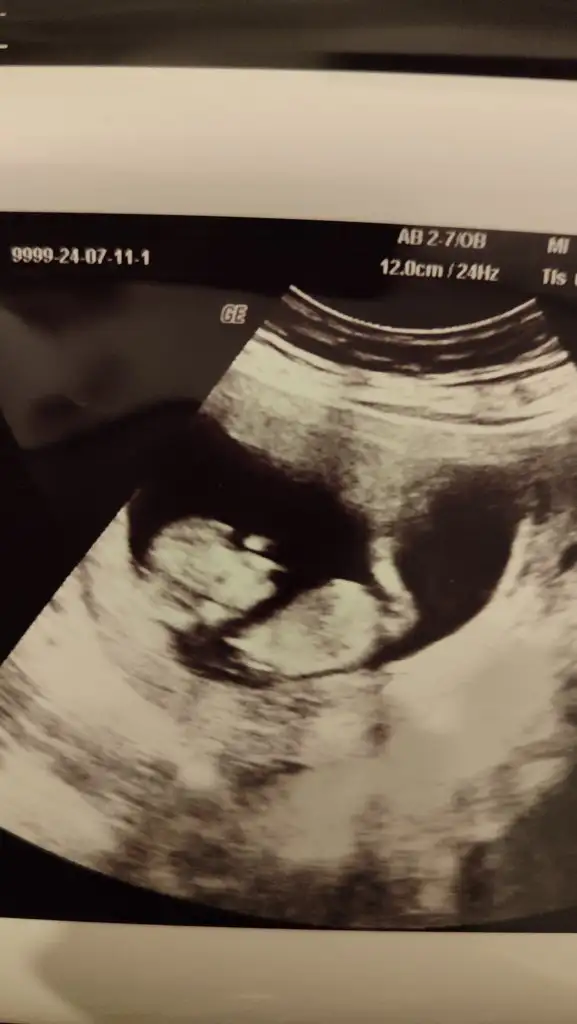

Biz bugün 12+0 dık. Doktor herşeyin yolunda göründüğünü söyledi. Gelişimi güzel görünüyor dedi. Folik asiti bıraktırdı 3 tane ilaç yazdı biri demir diğer ikisi ne bilmiyorum henüz almadım. Cinsiyet tahminlerinizi alırız ❣️

Eklentiler

• IMG_20240711_222412.webp

IMG_20240711_222412.webp

18,1 KB · Görüntüleme: 92

• IMG_20240711_222407.webp

IMG_20240711_222407.webp

17,7 KB · Görüntüleme: 81

• IMG_20240711_222357.webp

IMG_20240711_222357.webp

18 KB · Görüntüleme: 88